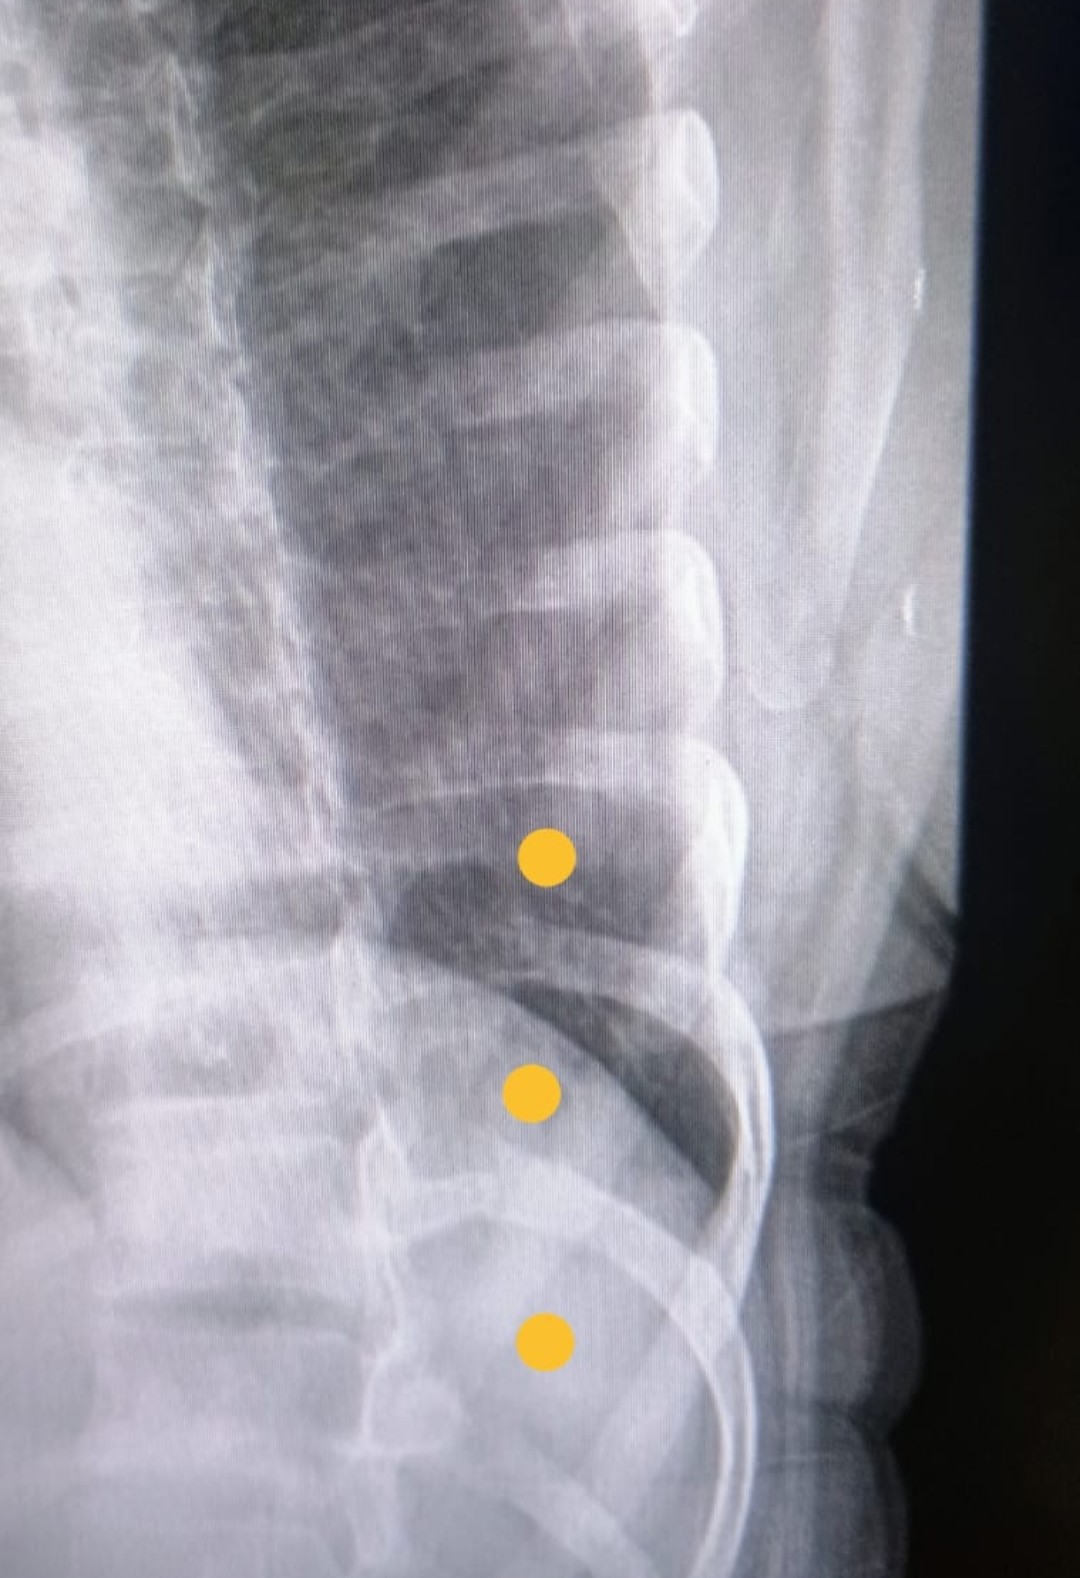

Após 8 dias de muita dor, retornou ao hospital em 18/07, onde finalmente foi diagnosticada com três costelas quebradas. Recebeu tratamento adequado e atestado de 15 dias para perícia do INSS.